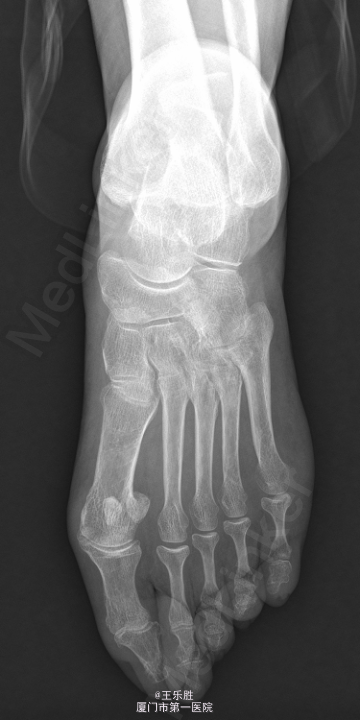

患者,女,58岁,因“左足跟疼痛半年”入院。患者半年前起无明显诱因下出现左足跟疼痛,行走时明显,休息后能缓解.

左足跟轻度肿胀,局部皮肤无红肿及皮温升高,轻压痛,左足背动脉搏动存在,肢端血运感觉正常,足趾活动尚可。MRI提示:“左足跟骨水肿”.

初步诊断:左足跟痛. 行CT(左下肢)检查提示:左跟骨骨折,断端稍嵌插、骨质增生样密度增高,跟骨结节骨质增生。余骨未见明显骨质异常,关节间隙如常.